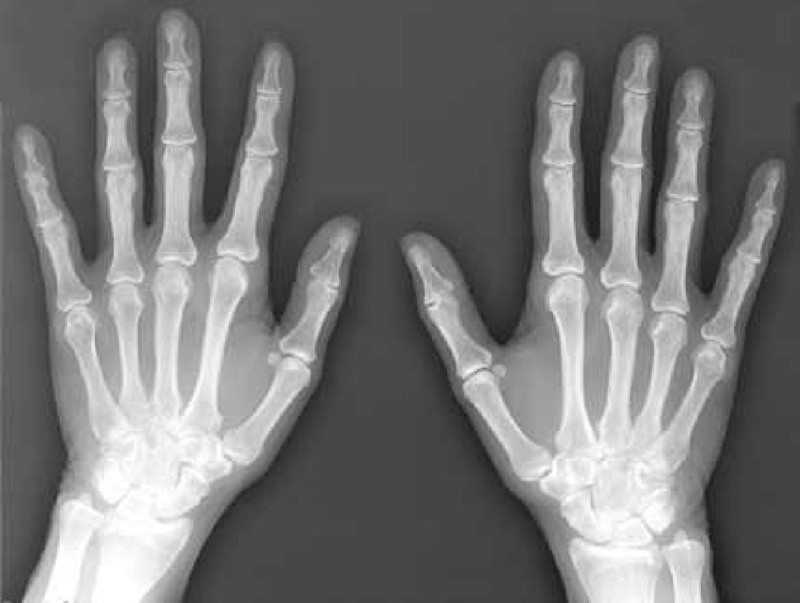

Quả là không bình thường khi mà thứ ánh sáng lại phát ra từ hộp các-tông màu đen dày được phủ lên ống cực âm. Thứ ánh sáng huỳnh quang xanh lục đó là tia X, được sinh ra thông qua một cách bí ẩn nào đó. Kêu vợ, bà Bertha, làm đối tượng thử nghiệm, nhà phát minh Rontgen khám phá ra rằng những tia X có thể đi xuyên qua các mô của cánh tay, nổi rõ hình xương tay. Việc Rontgen đột nhiên khám phá ra tia X đã trở thành một sự kiện chấn động toàn cầu. Cũng ngay trong năm 1895, người ta đã dùng tia X trong việc chẩn đoán gãy xương.